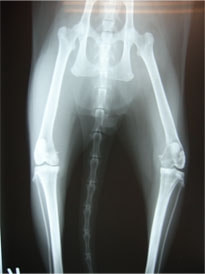

症例:右大腿骨遠位部の肉腫 クランバー・スパニエル 9歳 雌(未避妊)

2か月前から右後肢の完全挙上が認められ、消炎剤による内科治療で改善しないとのことで、他院から紹介来院した。

レントゲン検査

レントゲン検査所見から、骨もしくはその周囲組織に発生した腫瘍の可能性が考えられたため、病変部の細胞診検査およびジャムシディ生検針を用いた病変の骨生検を実施した。病理組織検査の結果、非上皮性の悪性腫瘍である“肉腫”と診断された。

内科治療に反応が乏しい四肢の跛行や疼痛は、本症例のように腫瘍が原因となっていることがあるため、レントゲン検査、骨生検等積極的に原因追及のための検査を実施することが必要である。骨の破壊を起こす悪性腫瘍は、非常に強い痛みを伴い、消炎鎮痛剤を用いても痛みを抑えることが困難となる。痛みの除去および腫瘍の治療のために断脚手術や抗がん剤等が必要となる場合があり、似た症状を示す整形外科疾患等とは治療法・予後が異なるため、その鑑別は重要である。